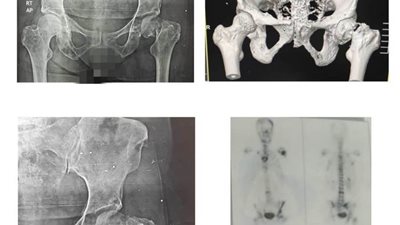

إجراء جراحة صعبة وخطيرة في مستشفى بئر العبد

الجمعة 09/يوليو/2021 - 06:07 م